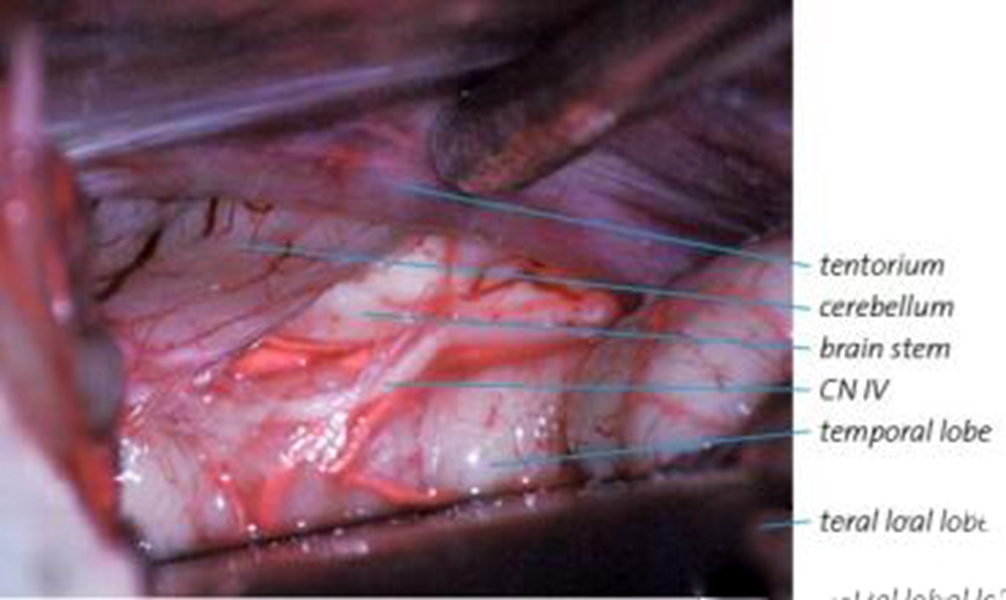

A:煙霧病目前有兩種手術方式,分別是血管搭橋手術和血管貼敷手術。血管搭橋手術是將顳淺動脈進行剝離,然後與大腦中動脈進行吻合搭橋。而血管貼敷手術是將顳淺動脈剝離後貼敷到腦的表面上。通過這兩種手術方式,主要的起到的作用是建立新的側枝循環,從而供應腦……